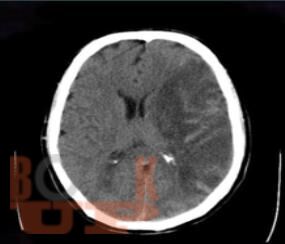

Интенсивная терапия внутричерепной гипертензии

Учебное пособие предназначено для ординаторов и слушателей курсов повышения квалификации по специальностям «Анестезиология и реаниматология», «Неврология», «Нейрохирургия». В настоящем учебном пособии освещены ключевые подходы к диагностике и оказанию помощи при внутричерепной гипертензии. Имеются тестовые задания и ситуационные задачи для самоконтроля знаний.